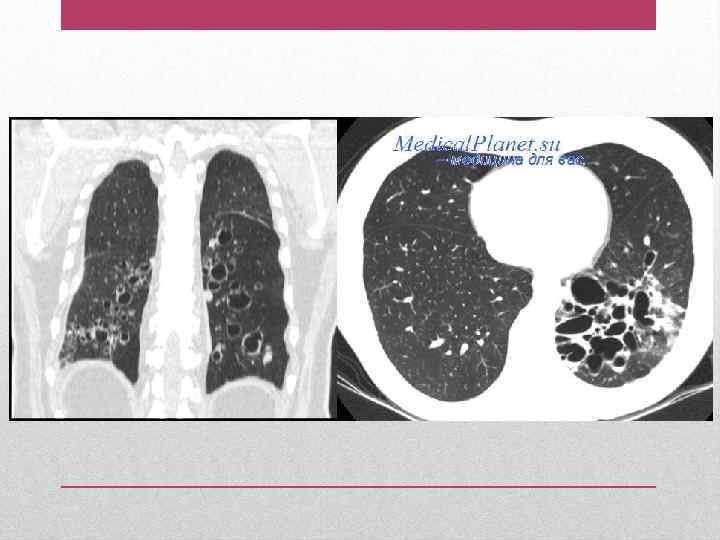

• Цилиндрические (умеренное расширение бронхов) • Веретенообразные (умеренное расширение и деформация бронхов и уменьшение числа делеций бронхов) • Мешотчатые (повреждение и фиброз проксимальных, затем дистальных бронхов с образованием «мешочков с гноем» ) • Кистоподобные • Смешанные • Варикозные (четкообразные – чередование расширенных участков бронха с участками, имеющими нормальный просвет) Форма

• Усиленный с деформацией легочный рисунок в нижних легочных полях, доходящий до периферических отделов легких, наличие ателектаза в нижних долях, средней доле, язычковых сегментах. • Ячеистый легочной рисунок в области нижних сегментов легких. • Тонкостенные кистоподобные просветления (полости) иногда с уровнем жидкости (при значительно выраженных мешотчато-кистозных бронхоэктазах в средней доле) • Уменьшение объема пораженных сегментов. Рентгенография органов грудной клетки

• • Проводится обычно в сочетании с бронхографией Уточнение локализации и типа бронхоэктазов Исключение опухоли инородного тела в бронхе Получение материала для бактериологического или цитологического исследования • Взятие биопсийного материала • Цилиндрические бронхоэктазы: линейные тени, достигающие периферии легкого без существенного сужения их диаметра. • Мешотчатые бронхоэктазы: множественные полукруглые тени различных размеров с горизонтальным уровнем жидкости ( «гроздь винограда» ) Бронхоскопия

• I стадия: цилиндрические бронхоэктазы в пределах одного легочного сегмента. • II стадия: распространенное поражение (1 -2 доли), участки фиброза легочной ткани, в периоды обострения – фокусы пневмонии. Компьютерная томография легких